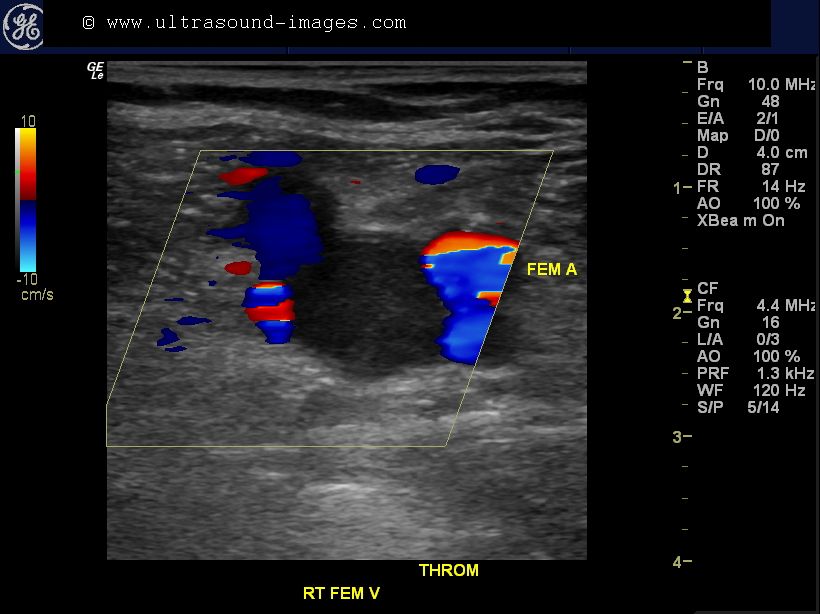

A bedside ultrasound was conducted to evaluate for DVT with clinical indications of edema and bother. The extremity was assessed at 3 locations – usual femoral vein, saphenofemoral junction, and the popliteal vein. Sequent compressions at these sites showed letter a noncompressible popliteal mineral vein. DVT is in attendance at the even of the ginglymoid joint vein.

Point-of-care (POC) ultrasound for the evaluation of deep vein thrombosis (DVT) is a two-region compression examination evaluating for clot in the femoral and popliteal regions.